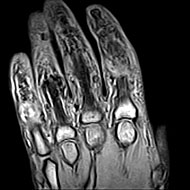

Hand MRI

Imaging the hand with MRI is useful for patients with tendon or ligament tears, fractures or other injuries.